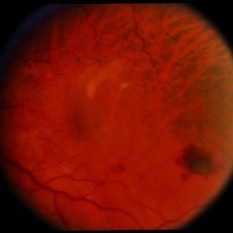

RPE Tear

RPE Tear

Sep 9 2014 by David Callanan, MD

78-year-old male, RPE tear.

Condition/keywords: retinal pigment epithelium